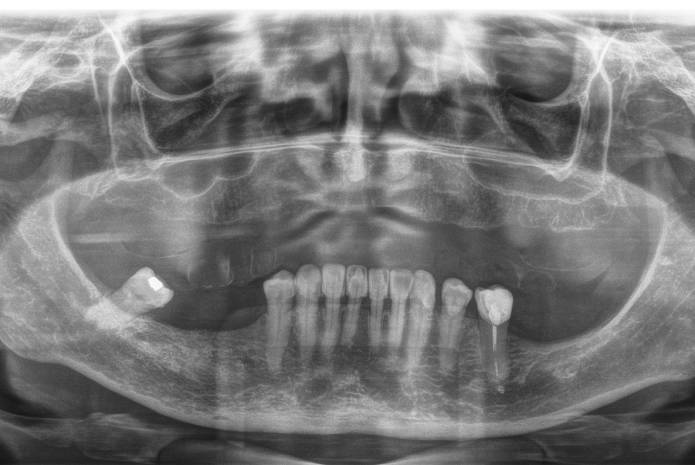

La arginina podría convertirse en un nuevo aliado contra la caries dental La fermentación de azúcares en nuestros alimentos por las numerosas bacterias de nuestra boca produce ácidos que destruyen…